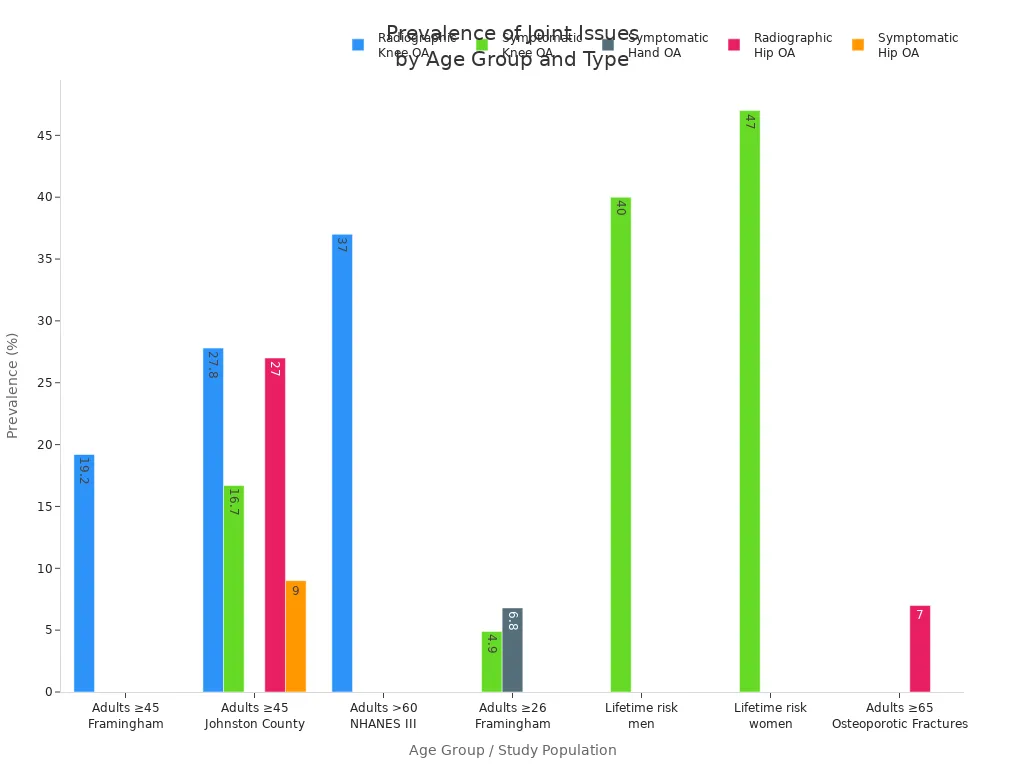

Adults ≥45 years (Framingham) | Radiographic Knee OA | 19.2% |

Adults ≥45 years (Johnston County) | Radiographic Knee OA | 27.8% |

Adults >60 years (NHANES III) | Radiographic Knee OA | ~37% |

Adults ≥26 years (Framingham) | Symptomatic Hand OA | 6.8% |

Adults ≥26 years (Framingham) | Symptomatic Knee OA | 4.9% |

Adults ≥45 years (Johnston County) | Symptomatic Knee OA | 16.7% |

Adults ≥45 years (Johnston County) | Symptomatic Hip OA | 9% |

Adults ≥65 years (Study of Osteoporotic Fractures) | Radiographic Hip OA (women) | ~7% |

Adults ≥45 years (Johnston County) | Radiographic Hip OA | 27% |

Lifetime risk (men) | Symptomatic Knee OA | ~40% |

Lifetime risk (women) | Symptomatic Knee OA | ~47%, rising to 60% with BMI ≥30 |